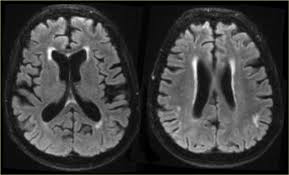

Lewy body dementia is typically diagnosed after other conditions are ruled out and the person's symptoms best fit with the diagnostic criteria for lbd. Related online courses on physioplus. Lewy body dementia stage 2 possibilities. Ct and mri show no characteristic changes in lewy body dementia but can initially help rule out other causes of dementia. Many people also experience changes in alertness including daytime sleepiness, confusion or staring spells. Read about the symptoms and what can help. Dementia with lewy bodies appears to be the second most common form of dementia, accounting for about one in five cases. Lewy body dementia, also known as dementia with lewy bodies, is the second most common type of progressive dementia after alzheimer's disease dementia.

Lewy, the scientist who discovered them. These deposits, called lewy bodies, affect chemicals in the brain whose changes, in turn, can lead to problems with thinking, movement, behavior, and mood. Many people also experience changes in alertness including daytime sleepiness, confusion or staring spells. Mri can show loss of brain cells (atrophy), but this occurs with other types of dementia too. Lewy body dementia stage 2 possibilities.

By this point, most caregivers are worried that something is seriously wrong and seek medical attention. These deposits, called lewy bodies, affect chemicals in the brain whose changes, in turn, can lead to problems with thinking, movement, behavior, and mood. Many people also experience changes in alertness including daytime sleepiness, confusion or staring spells. In lbd, protein deposits build up in the brain. Lewy body dementia (lbd) is a type of progressive dementia that leads to a decline in thinking, reasoning and independent function because. Dementia with lewy bodies or lewy body dementia is dementia caused by the presence of lewy bodies in the brain. Lewy body dementia (lbd) is often regarded as the second most common dementia in older individuals after alzheimer disease,1,2 possibly sharing the. Memory loss is not always an early symptom. How is lewy body dementia (ldb) diagnosed? Lewy body dementia symptoms include recent loss of memory, difficulty concentrating or paying attention, misperceptions of space and time. The deposits are called lewy bodies and are named after friedrich h. Mri can show loss of brain cells (atrophy), but this occurs with other types of dementia too. Protein deposits, called lewy bodies, develop in nerve cells in the brain regions involved in thinking, memory and movement (motor control).